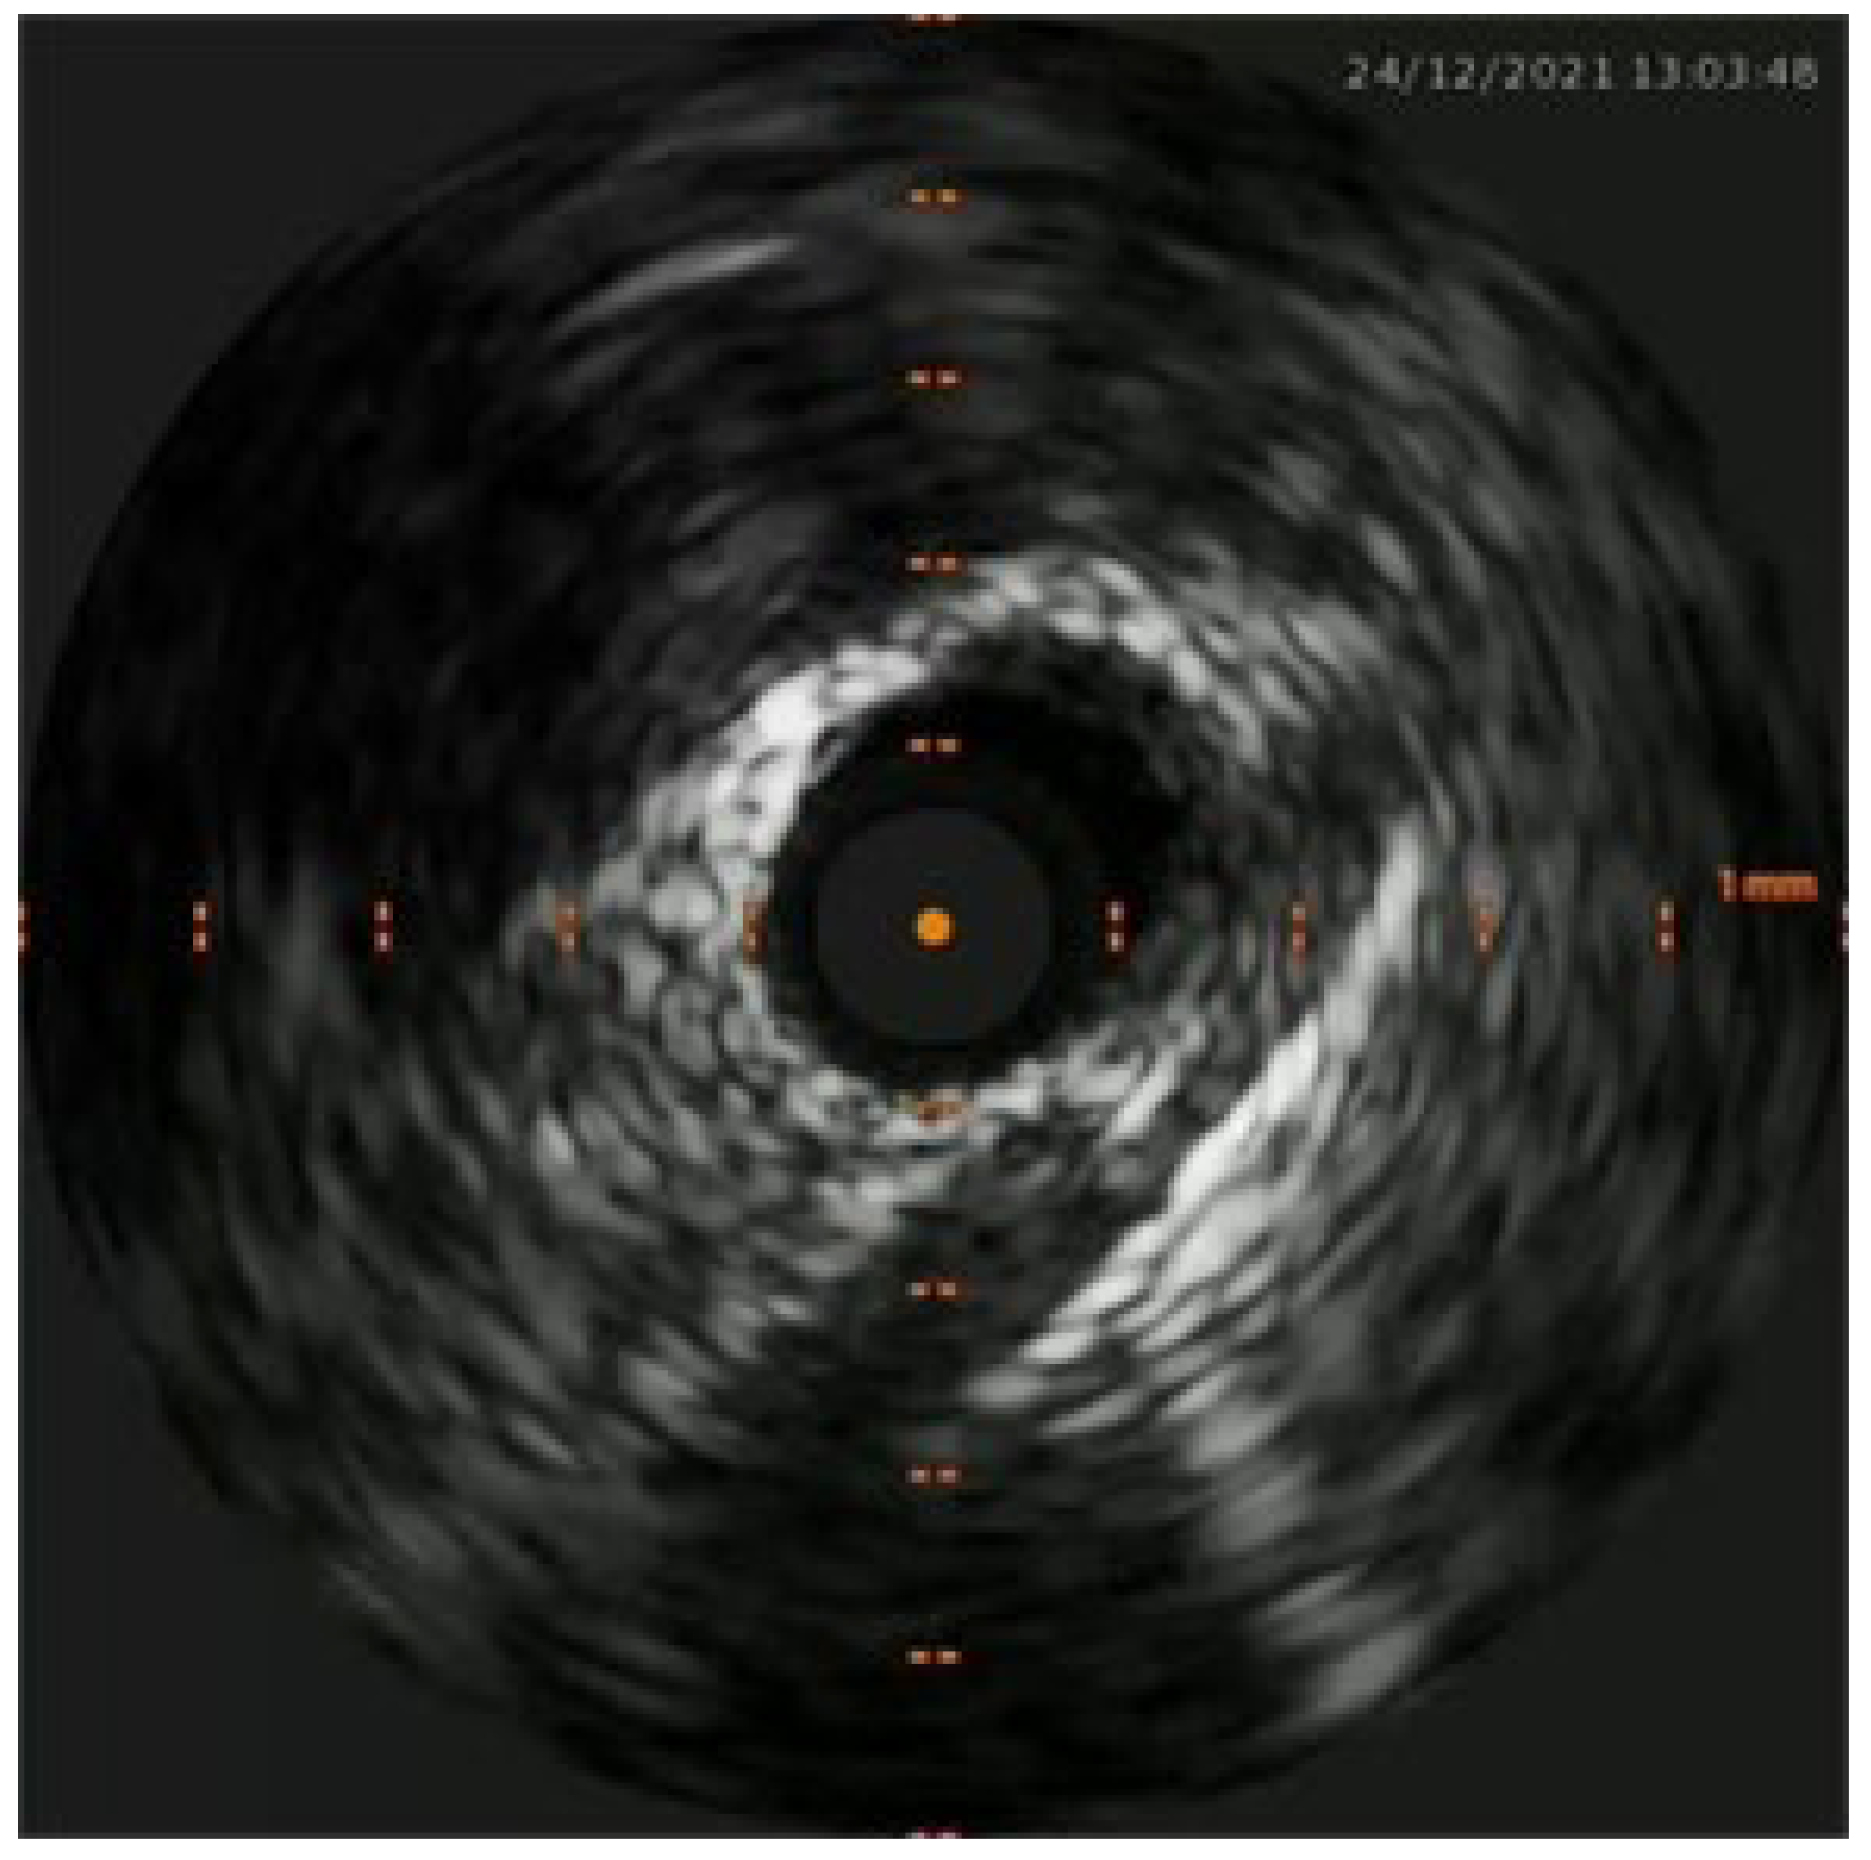

Percutaneous coronary intervention was therefore considered appropriate and a purposely undersized EBU 3.0 6F was selected. Regarding mechanical circulatory support only intra-aortic balloon pump was available. After rapid consultation, considering the insertion of the device, a decision was made to not proceed given the potential lengthening of the procedure, the need for femoral access and the issue of scanning the fetus with the XR detector. A safety wire, Terumo Runthrough floppy, was immediately placed on the patent left circumflex artery whilst after failing wiring on the left anterior descending with a Balance Middleweight wire a Sion wire was advanced up to the apical LAD. An IVUS run confirmed distal true lumen wire position showing a short subintimal track without compromise of any major side branch (Figure 2, Figure 3, Figure 4 and Figure 5).

Figure 4. IVUS showing distal true lumen.